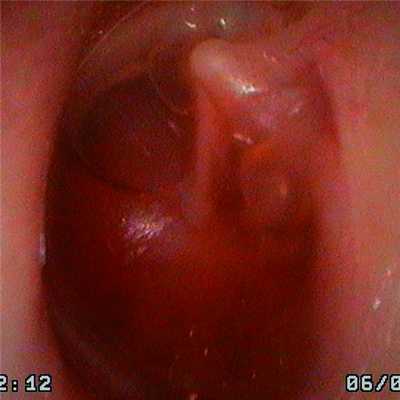

Даже у детей с ЭСО в секреторной стадии (1-я группа, 44 ребенка/74 уха) в 16 (36,4%) случаях/32 (43,3%) уха были выявлены ретракции I типа (по J. Sade). Более того, в 4 (9,1%) случаях/8 (10,8%) ушей были выявлены аттиковые ретракции I типа (рис. 1 на цв. вклейке). Рисунок 1. Аттиковая ретракция барабанной перепонки I типа. Экссудат в барабанной полости с включениями воздуха (секторная стадия). У 3 (6,8%) человек/6 (8,1%) ушей определен смешанный тип ретракций, когда ретракции располагались как в натянутой, так и в расслабленной частях барабанной перепонки. У 5 (11,4%) детей/7 (9,5%) ушей из этой группы выявлен выраженный мирингосклероз.